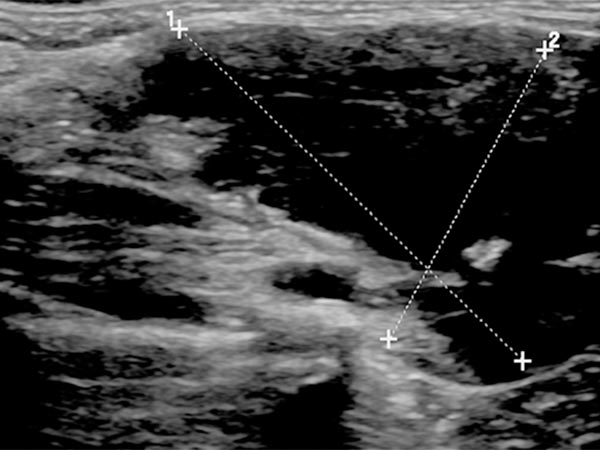

B-scan ultrasonography (longitudinal section) shows the venous malformation to be relatively homogeneously hypoechoic to anechoic. The venous dysplastic vascular channels are compressible with the ultrasound transducer and contain liquid blood.

B-scan ultrasonography (cross-section) also shows the venous malformation as combined hypoechoic to anechoic. The more echogenic parts correspond to sections of the venous malformation in which the contained blood has already clotted. In the anechoic portions, the contained blood is still liquid. In addition, a small phlebolith is found in the lesion, which is practically pathognomonic for a venous malformation.